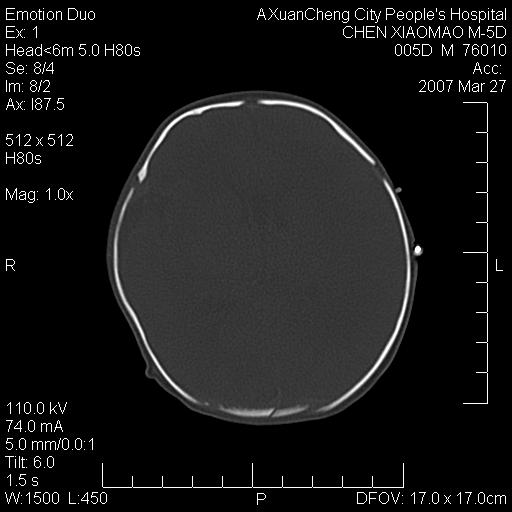

大家看看可有出血?另外枕骨中央是骨缝还是骨折

颅内未见明显异常。枕骨鳞部应为假缝(颅外软组织无肿胀),有外伤吗?

枕骨骨折可以下,应该比较明显,颅内还是正常的,不放心的话,短期随访。